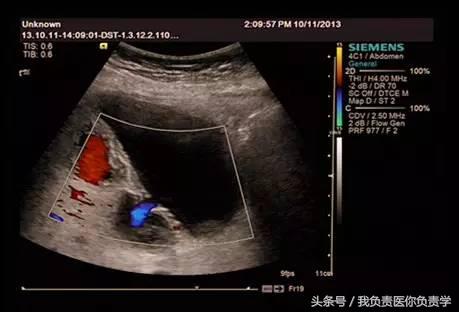

图3-图6示胆囊壁局部回声中断,探头加压及松开时CDFI可见红色及蓝色多普勒信号